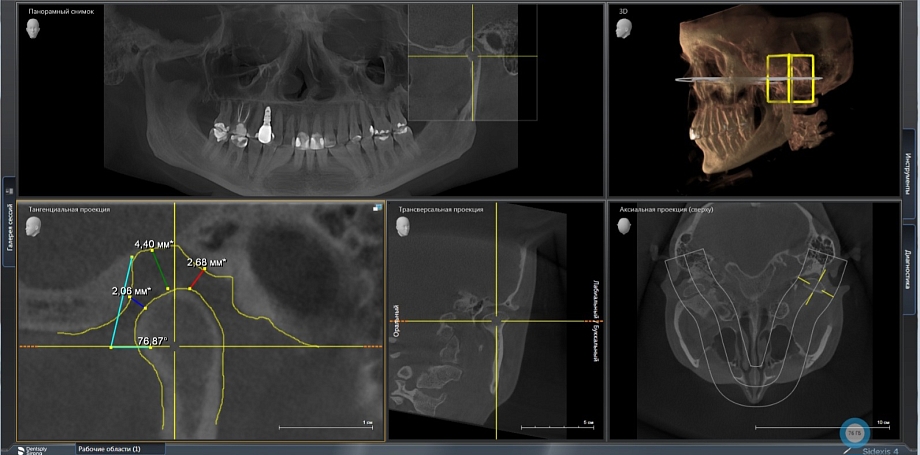

- Диагностика представляет собой несколько этапов. Диагностика состоит из статических и динамических методов исследования. Пациент сначала проходит статическую диагностику, которая включает: компьютерную томографию и теле рентгенографию позволяет определить состояние костных элементов височно-нижнечелюстного сустава и степень разрушения тканей и определить необходимые процедуры, цифровое сканирование зубов с использованием современных сканеров и фотографии позволяет получить точные данные зубных рядов для изготовления с помощью принтера 3Д моделей челюстей. К динамическим методам диагностирования относятся цифровая аксиография, которая с высокой точностью проводит запись движения ВНЧС при различных нагрузках и электромиографию, записывающую биопотенциал тонуса мышц при жевании.

Используется специализированная программа для симуляции движений челюсти и определения оптимального положения суставов. Данные загружаются и анализируются для определения необходимых коррекций, помогают найти патологии и определить утраченные параметры состояния всего зубочелюстного аппарата. Комбинация всех данных позволяет разработать точный план лечения, обеспечивая пациенту максимально оптимальные результаты в восстановлении зубочелюстной системы.

Мы предпочитаем работать с передовым оборудованием Sirona от компании Siemens, которая знаменита своим стоматологическим оборудованием. Это оборудование отличается исключительной надежностью и безопасностью для наших пациентов. Наш компьютерно-томографический аппарат Axeos Sirona обеспечивает всего 2,5 миллизиверта излучения на одно исследование, что является безопасным стандартом для пациентов. Для информации, суточная доза для маленьких пациентов составляет 100 миллизивертов, а для взрослых - 150. Благодаря этому, мы можем провести до 50 компьютерных томограмм в день, не превышая установленных лучевых норм.